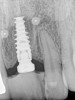

Proximity to Important Anatomic Structures

Panoramic and periapical radiographs are 2-dimensional (2-D) representations of a patient’s 3-D anatomy. Differences in radiographic machines and techniques can lead to image distortion, such as elongation and shortening of anatomy. Accurate evaluation and measurement of the relationship between the mental nerve, inferior alveolar nerve (Figure 4), or nasopalatine/incisive nerve, and the planned implant position can best be determined and planned by a 3-D evaluation of the anatomy as related to the planned restoration.3,30 Implant placement in patients in whom there is a question of nerve or sinus proximity is most accurate using “virtual” treatment planning and placement using CT-generated guides, thus minimizing potential patient morbidity. Technologies such as “all-on-four,” which is designed to maximize the intra-arch spread of implant platforms while avoiding the mandibular nerve and maxillary sinus, are excellent indications for CT-guided implant surgery (Figure 5 and Figure 6).